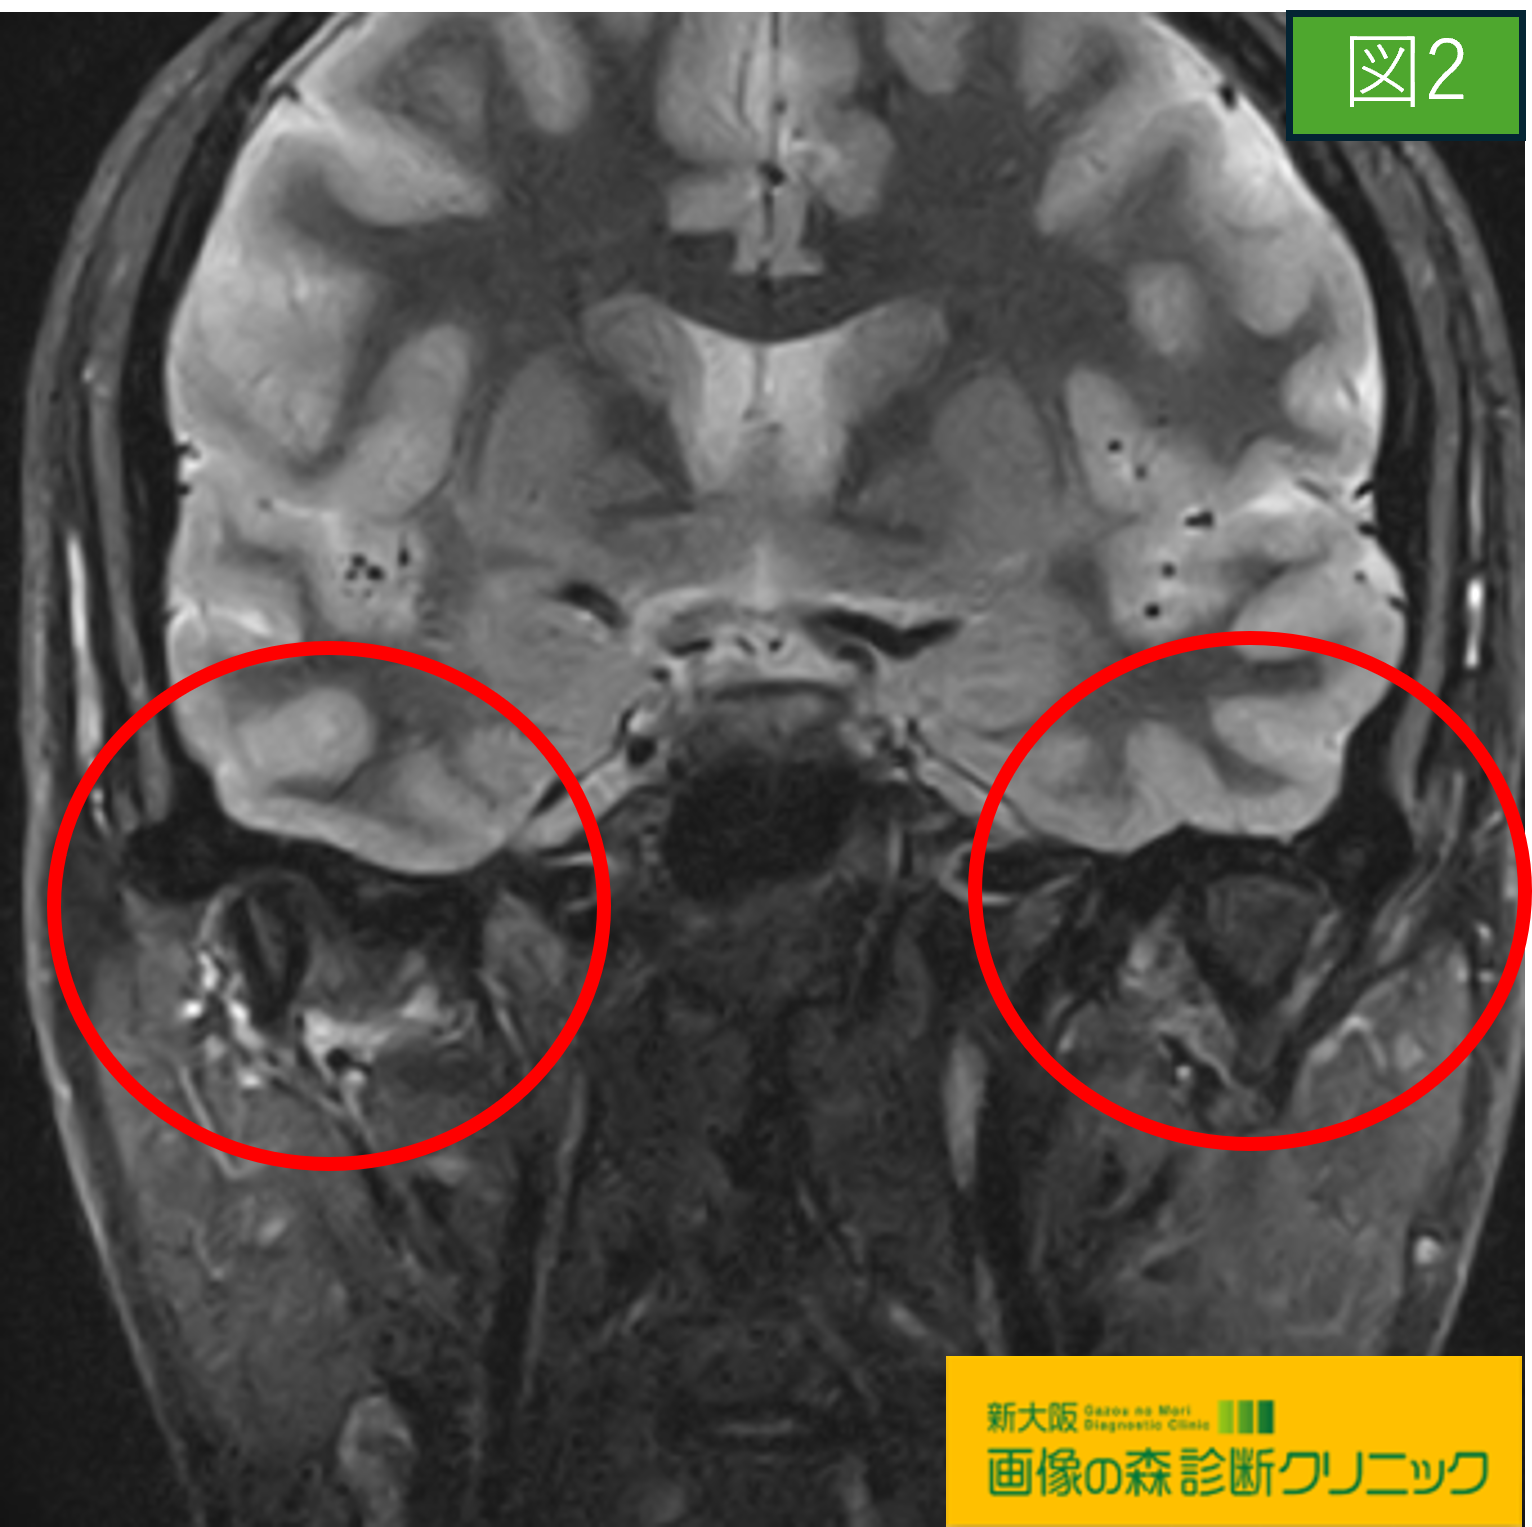

図2・図4では変形性顎関節症の症例を示しています。

〇図1・図2の画像は顎関節部を前から見た画像であり、

それぞれの赤〇内にご注目下さい。

図2の症例画像では、両サイドを比較しても、

右下顎部が変形しており、その周りの咀嚼筋が

炎症を起こしています。